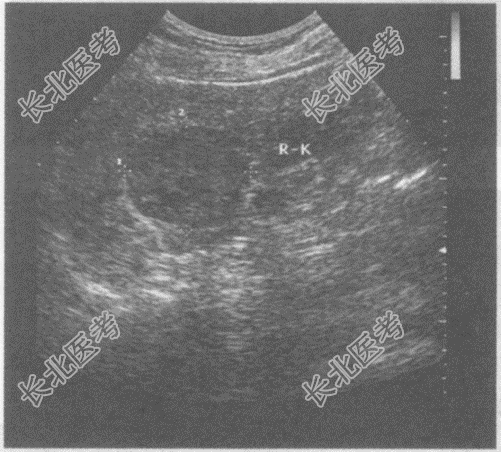

- 单项选择题临床资料:女, 52岁,自述无痛性肉眼血尿3天。

化验检查: 尿常规红细胞满视野。

超声综合描述:右肾上极可见4.3cm×3.7cm低回声区, 边界清晰,形态规则, 向包膜外突起,CDFI: 低回声区周边可见丰富动静脉血流信号。见下图及彩图。